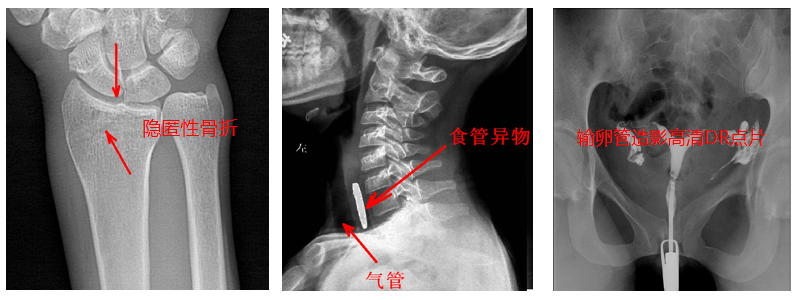

4.數字造影。PLD5500B動態DR機適用于各種普通及特殊造影,如口服膽囊造影、靜脈膽道造影、T管造影、逆行胰膽管造影(ERCP)、靜脈腎盂造影(IVP)、子宮輸卵管造影、脊髓造影等,主要應用于消化內外科、泌尿外科、婦科、神經內外科等。

5.準確點片。在透視下準確找到病灶部位,這對于早發現隱匿性骨折有著不可替代的作用。更難能可貴的是,它可以在透視情況下進行整骨復位以及術后在透視下檢查。